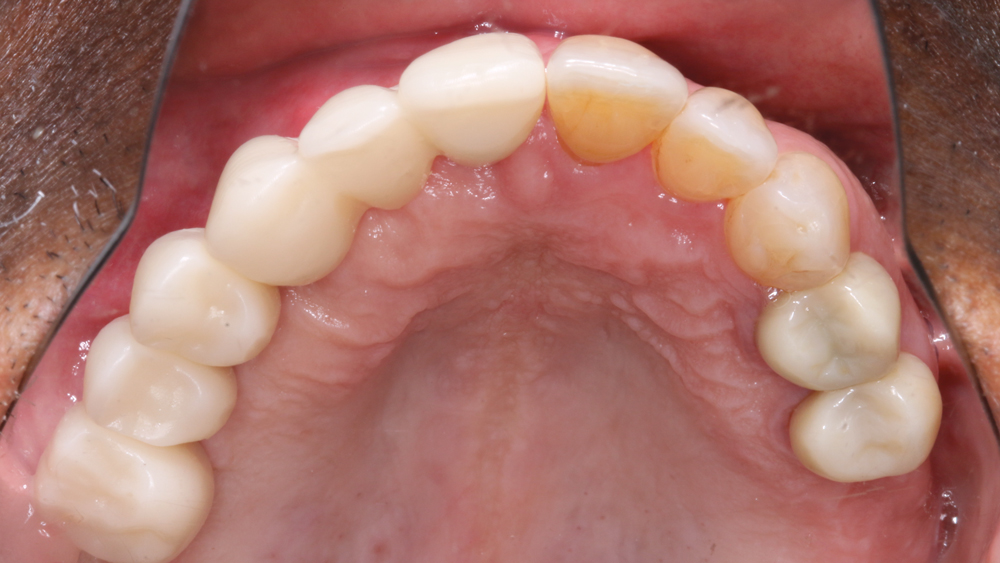

There was significant bone loss on the right side of the maxilla, from the existing non-restorable central incisor back to the second molar. With this bone loss and mobility of the teeth, there was vertical and horizontal deficiency of the available bone. Options considered included an autogenous block graft to attempt to increase bone height and width. The second option was to work with the available bone, extract the non-restorable teeth on the right side of the maxillary arch, immediately place implants, and create esthetics with a longer prosthesis that includes pink-colored gingival areas. A BruxZir Solid Zirconia implant bridge was the optimal long-term solution because the entire prosthesis, including the gingival areas, is milled from a single block of high-strength solid zirconia, affording unmatched durability for this type of restoration. Although Weldon did not have a high smile line, he was attracted to a prosthetic design that included gingival areas to restore esthetics where tissue loss had occurred.

RESTORATIVE TECHNIQUES FOR ESTHETICS AND OCCLUSION

Esthetics and occlusion can be challenging in these types of cases. Restoring half an arch and trying to mirror the contralateral soft tissue and dentition with proper contours and shade requires patience and resolve. The lab provided a PMMA try-in prosthesis, which I evaluated with Weldon. The try-in allowed us to easily resolve any discrepancies with the prosthetic design and develop ideal occlusion. Once Weldon agreed on the esthetics, the PMMA provisional was returned to the lab and duplicated in BruxZir Solid Zirconia. This extra step eliminates excessive chairside adjustments upon seating of the final prosthesis.

BruxZir Solid Zirconia has proven to be extremely strong yet compatible with opposing natural dentition; the material exhibits minimal wear on the opposing enamel. Its color and shading are extremely natural in appearance, and I have no concerns about chipping or cracking of the material over time. The final seating of the prosthesis was straightforward, and I have confidence that the material is a long-lasting solution. Weldon was thrilled with the final restoration, as we were able to surpass his expectations and provide him with a fixed, functional, esthetic result.